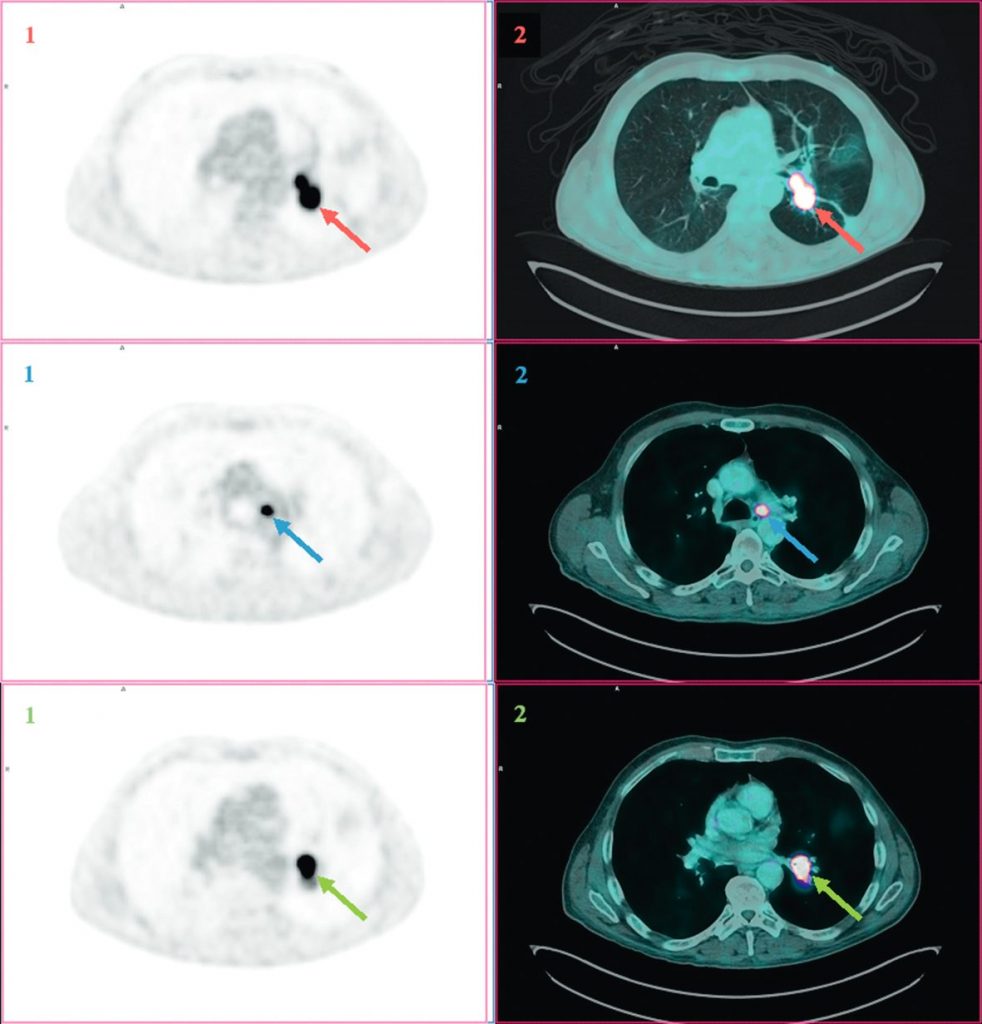

Fig. 101.4. Images TEP au 18FDG (1) et TEP au 18FDG fusionnée à la TDM (2) en coupes axiales.

Réalisées dans le cadre du bilan d’extension d’un carcinome bronchopulmonaire non à petites cellules lobaire inférieur gauche (flèche rouge).

Hyperfixation pathologique en regard d’adénopathie hilaire homolatérale (flèche verte) et de la fenêtre aortopulmonaire (flèche bleue).

Source : CERF, CNEBMN, 2022.

La TEP-TDM au 18FDG possède de meilleures sensibilité et spécificité que le scanner pour prédire l’envahissement lymphatique (figure 101.4).